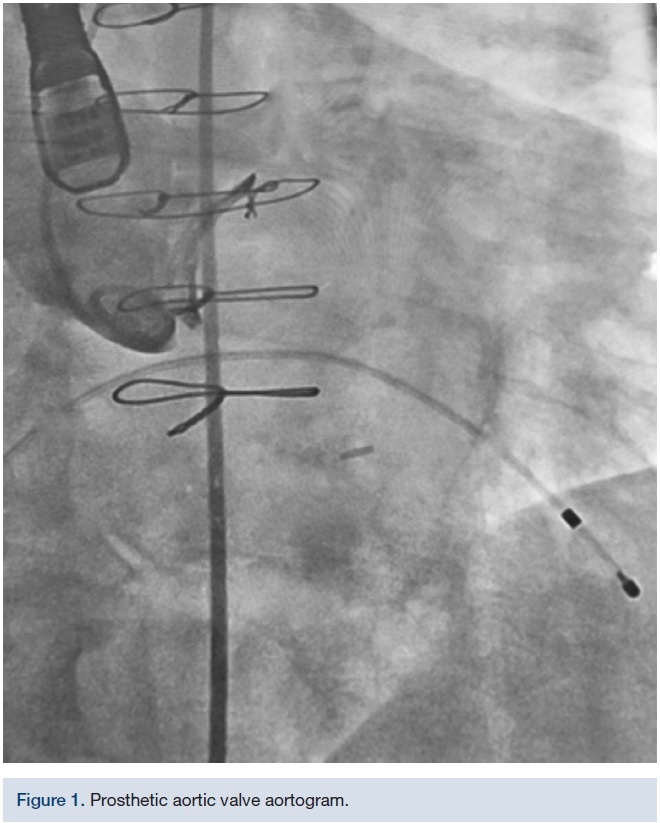

The initial TAVR was attempted in the hybrid operating room (OR) with the heart team once the patient’s viral load was 104 Iu/ml and platelet count was 89,000. The left femoral artery was accessed with a 6 French (F) sheath and a 6F straight pigtail was advanced over a standard .035-inch wire into the non-coronary cusp of the ascending aorta. The left femoral vein was accessed with a 6F sheath and a temporary pacing wire was placed. A cutdown was performed on the right femoral artery, serially upsizing to an 18F DrySeal sheath (Gore Medical) over a .035-inch Lunderquist extra stiff wire (Cook Medical). A 6F Judkins Right (JR) 4 catheter was advanced over a standard wire in an attempt to cross the aortic valve under fluoroscopy and 3D echo/transesophageal echocardiogram (TEE) guidance. A variety of wires and catheters were attempted (.035-inch Rosen wire [Cook Medical], .035-inch Cook straight tip [Cook Medical], Merit .035-inch angled Glidewire, .035-inch Lunderquist extra stiff straight wire, Steelcore .018-inch extra support [Abbott Vascular], 6F Amplatz Left1, 6F JR4, 6F MPA [Cardinal Health], 6F IM, 6F H-stick guide [Cardinal Health], and 6F straight and angled pigtail catheters), but the operators were unable to successfully cross the prosthetic stenotic aortic valve in a retrograde fashion. After 2.5 hours, the case was aborted.

The 18F DrySeal sheath was placed through the right common femoral artery over an .035-inch Lunderquist extra stiff wire. A 4F micropuncture needle was advanced through the apical window into the left ventricular cavity. A micropuncture wire was advanced antegrade across the aortic valve into the ascending aorta. Finally, the micropuncture sheath was advanced over the wire into the ascending aorta, and the micropuncture needle and wire were removed. An .035 inch x 300 cm Supra Core 35 wire (Abbott Vascular) was advanced via the transapical sheath into the ascending aorta and ultimately, to the descending aorta. The transapical sheath was then removed. A triple-lobed EN Snare Endovascular Snare System (Merit Medical Systems) was inserted into the 18F femoral arterial sheath and the Supra Core .035-inch wire was trapped. Subsequently, a 6F pigtail catheter was advanced over the snared Supra Core .035-inch wire and placed into the left ventricle. The Supra Core .035-inch was replaced by a 260 cm Amplatz .035-inch Super Stiff wire (Boston Scientific) and advanced into the left ventricle through the pigtail catheter. The pigtail catheter was removed and an 18 mm Z-Med II balloon (B. Braun Interventional Systems) was inserted over the Amplatz super stiff wire. A standard balloon aortic valvuloplasty was performed in preparation of the valve positioning. After the balloon valvuloplasty, a 23mm CoreValve Evolut R was successfully deployed. A 22 mm True Dilatation balloon (Bard Peripheral Vascular) was utilized to perform post dilation aortic balloon valvuloplasty. The final result was a mild aortic insufficiency with a 5 mm transvalvular gradient.